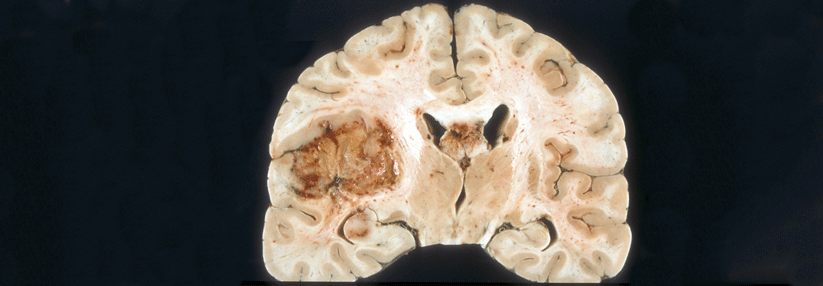

Unheilbare Hirntumoren bilden diffus infiltrierende Netzwerke und die Kommunikation untereinander sowie mit gesunden Neuronen vermittelt den Zellen Überlebensvorteile. Indem man diese Verbindungen angreift, lassen sich zumindest im Labor Therapieresistenzen überwinden.

Da sie das Gehirn diffus kolonisieren, stellen unheilbare Hirntumoren Erkrankungen des gesamten Organs dar, erklärte Prof. Dr. Frank Winkler vom Universitätsklinikum Heidelberg. Dabei bedienen sie sich neuronaler Mechanismen und bilden neuritenähnliche Fortsätze und Netzwerke aus. „Man sieht, dass das gesamte Gehirn von diesen Tumorauswüchsen infiltriert ist“, schilderte der Experte. Eine Resektion alleine löse das Problem nicht.